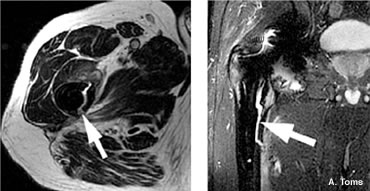

I have a patient who was in his mid thirties at the time of the index procedure in 1997 with a metal on metal poly sandwich who has radiolucency, but no revision. I have a patient who had a 38mm MoM in about 2005 who developed a large cyst which extended up into the psoas. She saw an out of state physician who ordered an aspiration arthrogram suspecting infection, but the fluid came back perfectly clear. This was in 1997. The radiologist called me and asked if he could inject a steroid. I gave him the go ahead. The cyst resolved, the repeat MRI showed resolution and the patient continues to do well. |